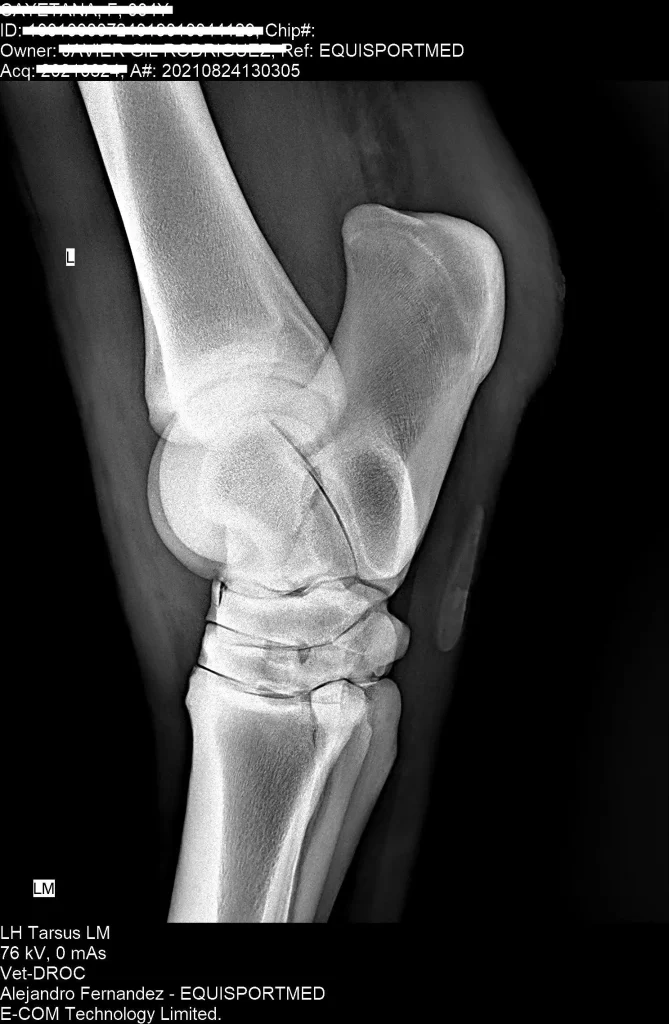

Advanced Diagnostic Imaging

We carry out diagnostic tests such as scintigraphy, magnetic resonance imaging, among others, in collaboration with equine veterinary hospitals.